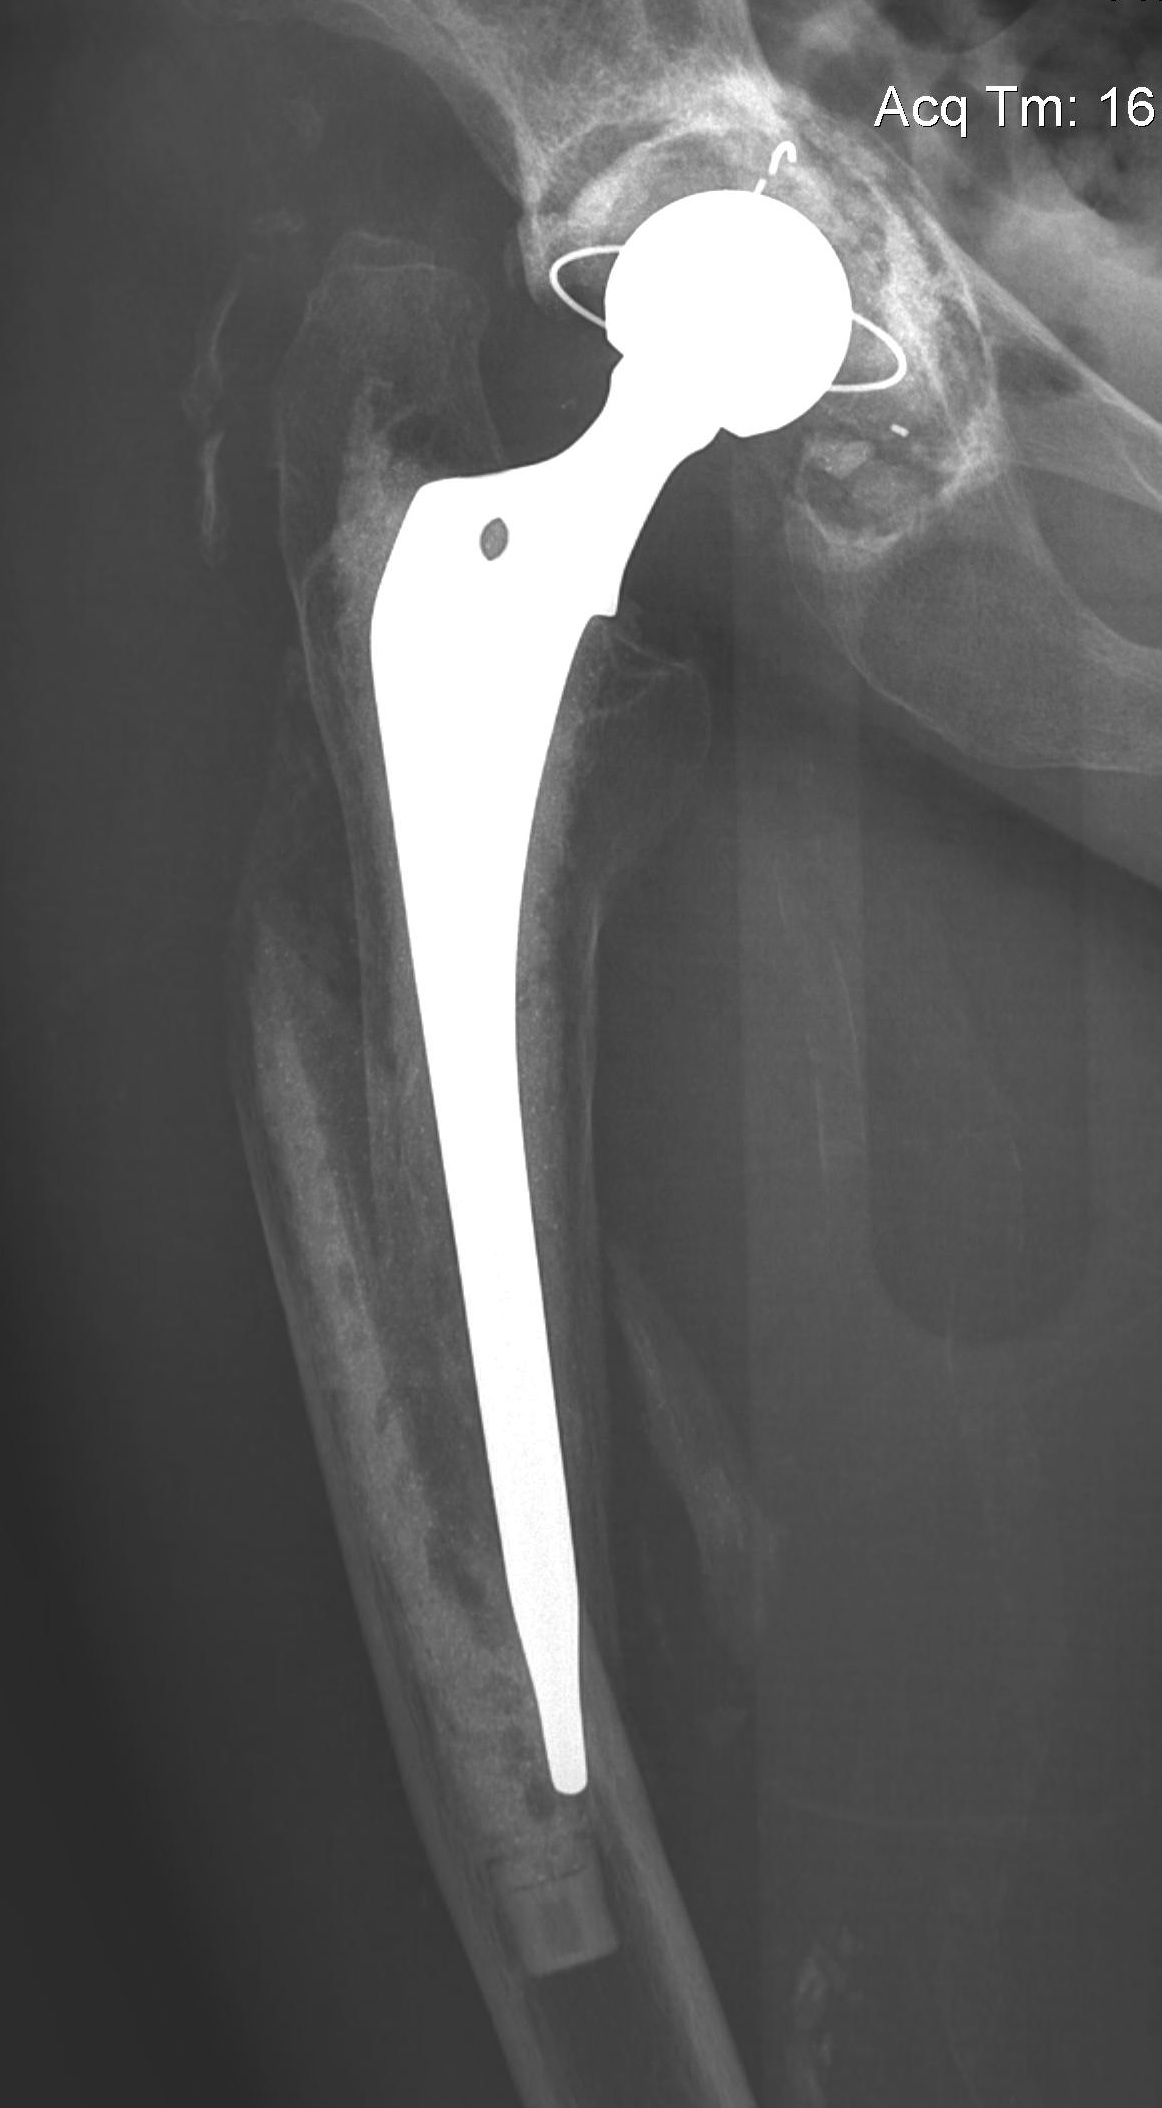

Long stem cemented revision